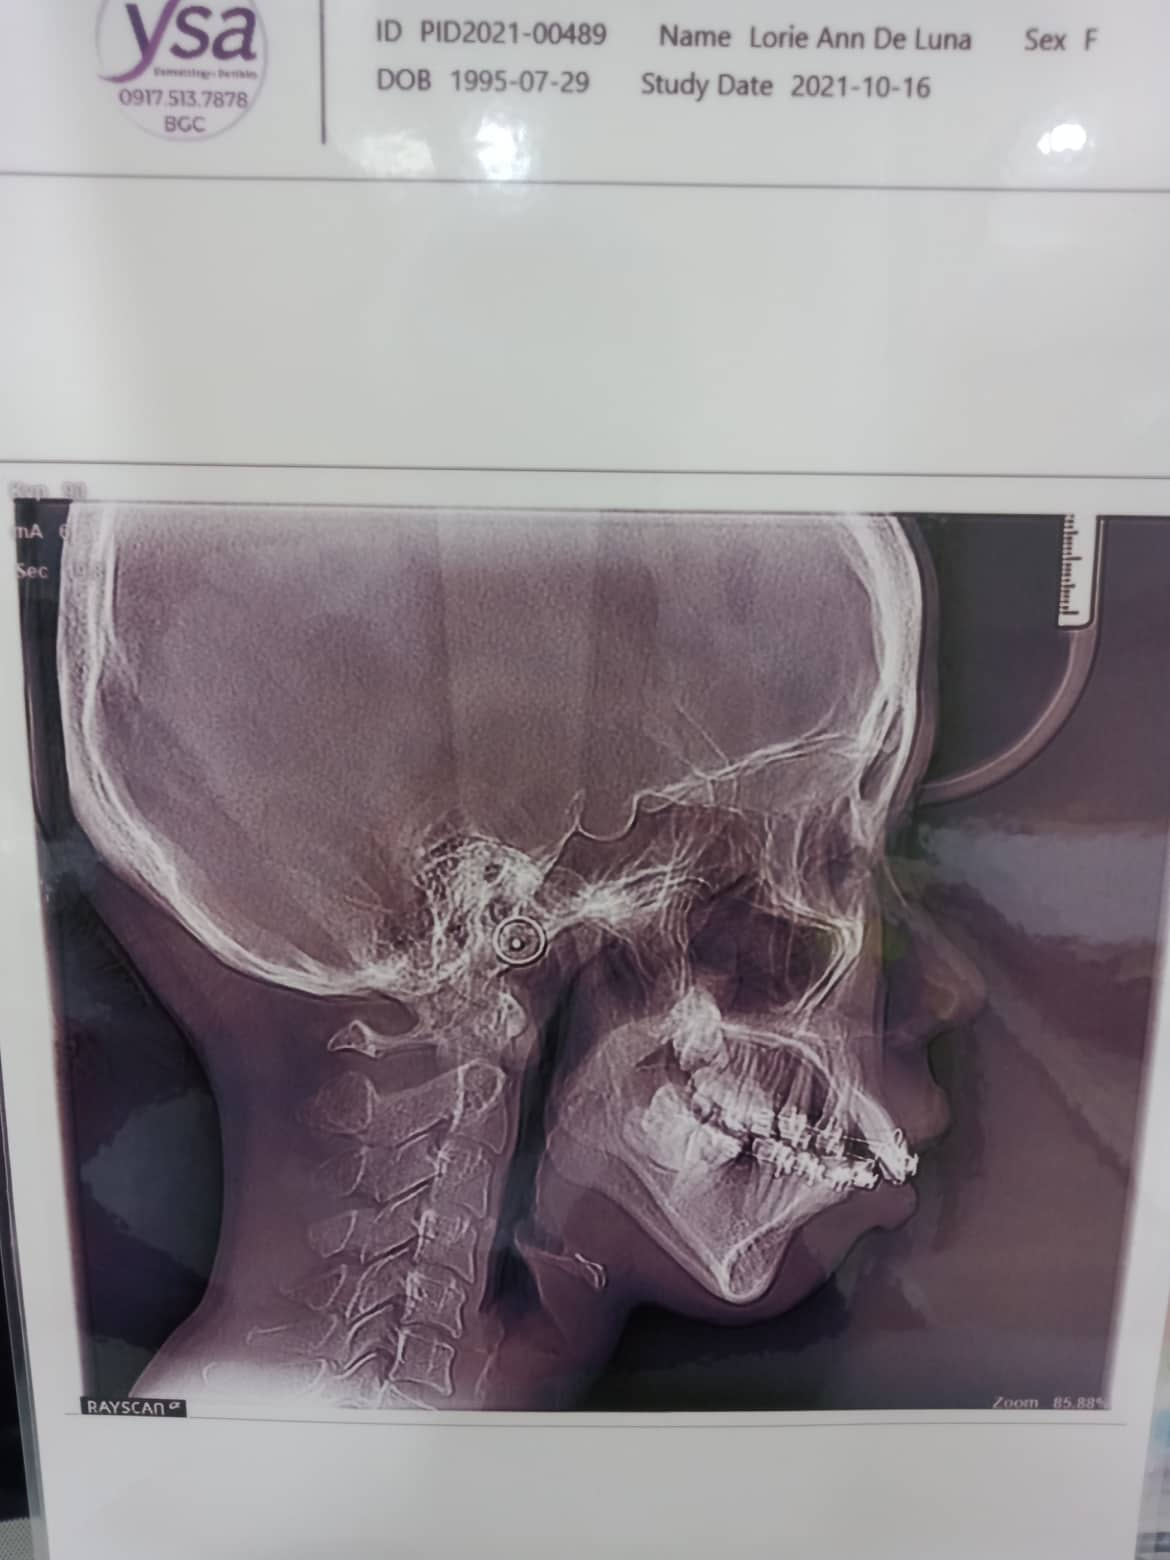

- De Luna

- Lorie Ann

- July 29, 1995

- 08/15/21- 16ssU/16nitiL class 2 elastic fox- distalize 3' reattached 46 09/18/21 adj- enmass UPPEr 16ss L/16*16ssU fox elastic class2 10/23/21 - 16x16ssU/ 16ssL enmass upper- penguin class 2 *req molarband 4 11/23/21 - class 2 pengiun enmass 12/18/21- Adj Same wire Rabbit enmass Reattached 37 01/22/22- adj 16x16 ss U/ 18 niti L box elastic posterior LR - penguin 3/12/22 - 18niti U/ RC 18 niti/ box elastic fox 15-16 to 44-45/ 25-26 to 34-35/ ortho relief laser 4/1/22- 18 niti u/ L 18 Rc box elastic penguin occ pads 17/ 37 osseointegration laser on upper anterior rettached (new bracket) 45 09/20/22 16X16 SS u/ SAME WIRE LOWER rc 18/ BOX ELASTIC FOX/ REATTACHED 45 10/15/22- 16x16ss u/ 18ssL RC 43/44/45 for incisal restoration 11/15/22- adj 01/06/23- ADJ/2REATTACHED 02/04/23- ADJ 3/11/ - Adj same / laser tmj / #27 Caoh (Temp). 04/1/23- 16x16 UL/chain U 05/16/23- UL - Same wire/Reattach #35/Resto #27 1 surface 07/22/23- same wire/ Individual power O's Upper 08/18/23- same wire/stabilization 09/05/23- same wire Fox/ class 2 10/20/23- same wire /reattached 46, rabbit class 2 **removal of Braces October or November LATE: January 2,300 monthly adjustment. 11/18/23-Same wire; Oral prophylaxis; suggested odontectomy on upper molars first to prevent further increase of overjet